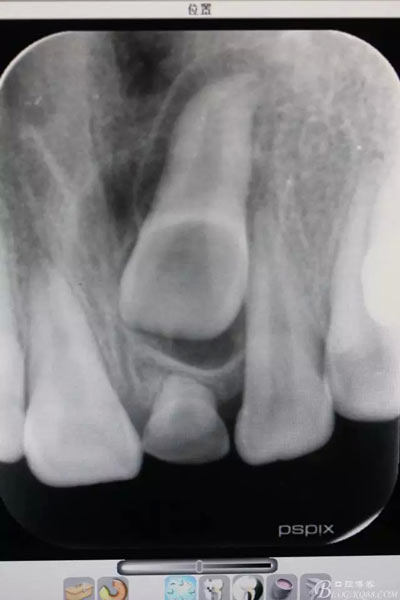

圖1.術(shù)前根尖片影像檢查:21根尖1/3彎曲,牙冠上方有一致密團塊影。左乳Ⅰ滯留

圖20.術(shù)后的根尖片影像檢查:21移動約 3mm距離,牙冠方向基本正常,半年后復(fù)查,定正畸治療方案